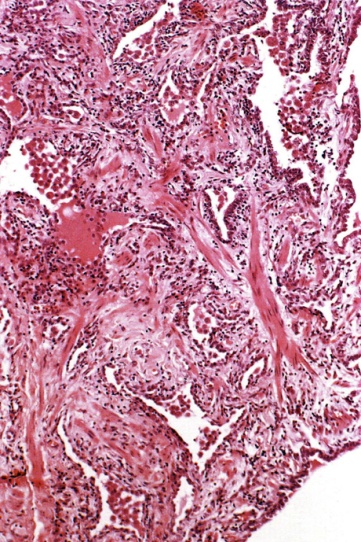

Radiační pneumonitida je definována jako exsudativní zánět vznikající jako následek ionizujícího ozáření a je považována za alveolitis z poškození pneumocytů a endoteliálních buněk. Poškození se manifestuje obvykle za 4 - 6 měsíců po ozáření plic jednorázovou dávkou 8 Gy a vyšší. Jedná se o změny v ozářených oblastech a jsou tedy ohraničené. Radiační pneumonitida se klinicky projevuje pod obrazem nehnisavého exsudativního zánětu, tj. dušností, neproduktivním kašlem, teplotou a pleuritickou bolestí. Objektivně se u sledovaných pacientů zjišťuje přítomnost chrůpků a horečky. V případě dekompenzace nemoci se rozvíjí akutní respirační nedostatečnost nebo akutní cor pulmonale. Při histologickém vyšetření v manifestační fázi jsou popisovány intersticiální intraalveolární edém, zánětlivá infiltrace alveolů, zmnožení makrofágů a zvýšená buněčnost vazivové tkáně. Prognóza nemoci záleží především na léčbě, ale i při použití současných léčebných možností umírá asi čtvrtina až polovina všech nemocných.

Radiační fibróza plic, tj. zmnožení fibrózní plicní tkáně, je konečným stádiem postradiačních plicních změn. Radiační fibróza plic je syndromem, který se objevuje po ozáření plicní tkáně ionizujícím zářením až po 30 týdnech a jako u radiační pneumonitidy po dávkách větších než 8 Gy. Ionizujícím zářením způsobené nekrotické změny jsou hojeny fibrotickou jizvou. Avšak proces hojení u ozářených tkání není stejný jako u konvenčních poranění, nýbrž je aktivován i několik let a fibrotické jizvy reprezentují nepravidelně uspořádaná kolagenní vlákna.